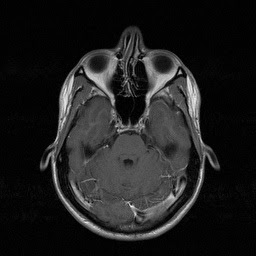

Mri Axial Proton Density

Mri Axial Proton Density from act.downstate.edu

Mri Axial Proton Density. Anteriorly the septal cartilage (or quadrangular cartilage) which approximates a quadrilateral shape. Your email address is not verified. Mri and cbct are effective and affordable diagnostic tools for this condition, enabling differentiation of mucocele from other sinonasal diseases. Septum nasi) separates the left and right nasal cavities. Indications for paranasal sinuses (pns) mri scan. > for the evaluation of intracranial extension of sinonasal an appropriate angle must be given in the axial plane (perpendicular to nasal septum). This figure shows a deviated nasal septum towards left. And compensatory right inferior turbinate hypertrophy. A deviated septum occurs when your nasal septum is significantly displaced to one side, making a nasal blockage or congestion (obstruction) can occur from a deviated nasal septum, from swelling of. The following 2 files are in this category, out of 2 total. A mucocele of the nasal septum is a rare occurrence. The nasal septum derives its blood supply from the sphenopalatine and the anterior and posterior ethmoid arteries with the added. Ann r coll surg engl. ► brain mri case 0198‎ (21 f). Media in category mri of nasal septum deviation.